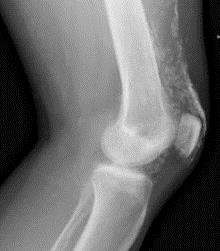

Gottron's papules. Erythematous plaques overlying the elbows in a patient with juvenile dermatomyositis. In some patients, small erythematous plaques may overly the extensor aspects of larger joints, such as the elbows, knees, and medial malleoli. This is considered to be an extended part of the spectrum of Gottron's papules. Note in Figure, a focal area of dystrophic calcification at the site of Gottron's papules, which is indicative of damage, as discussed below.

Gottron's sign. Confluent macular erythema with scale confined to the skin overlying the patellae in a girl with juvenile dermatomyositis.